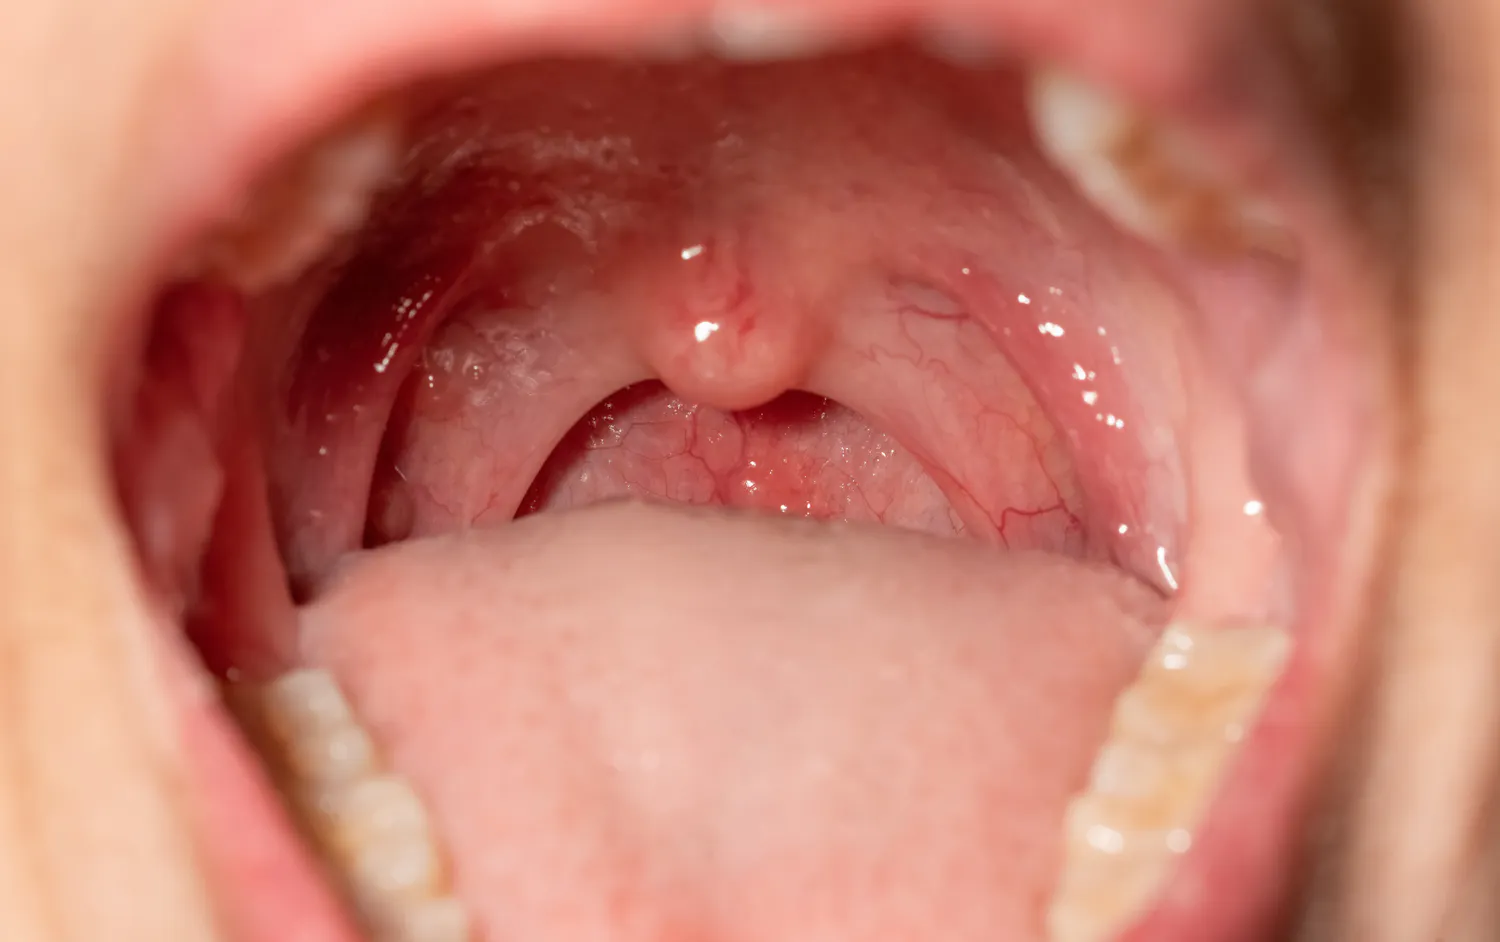

Le « syndrome de la fellation vigoureuse » désigne une série de symptômes qui peuvent survenir après une fellation un peu trop intense…

Le « syndrome de la fellation vigoureuse » désigne une série de symptômes qui peuvent survenir après une fellation un peu trop intense… Lire la SuiteSanté Magazine